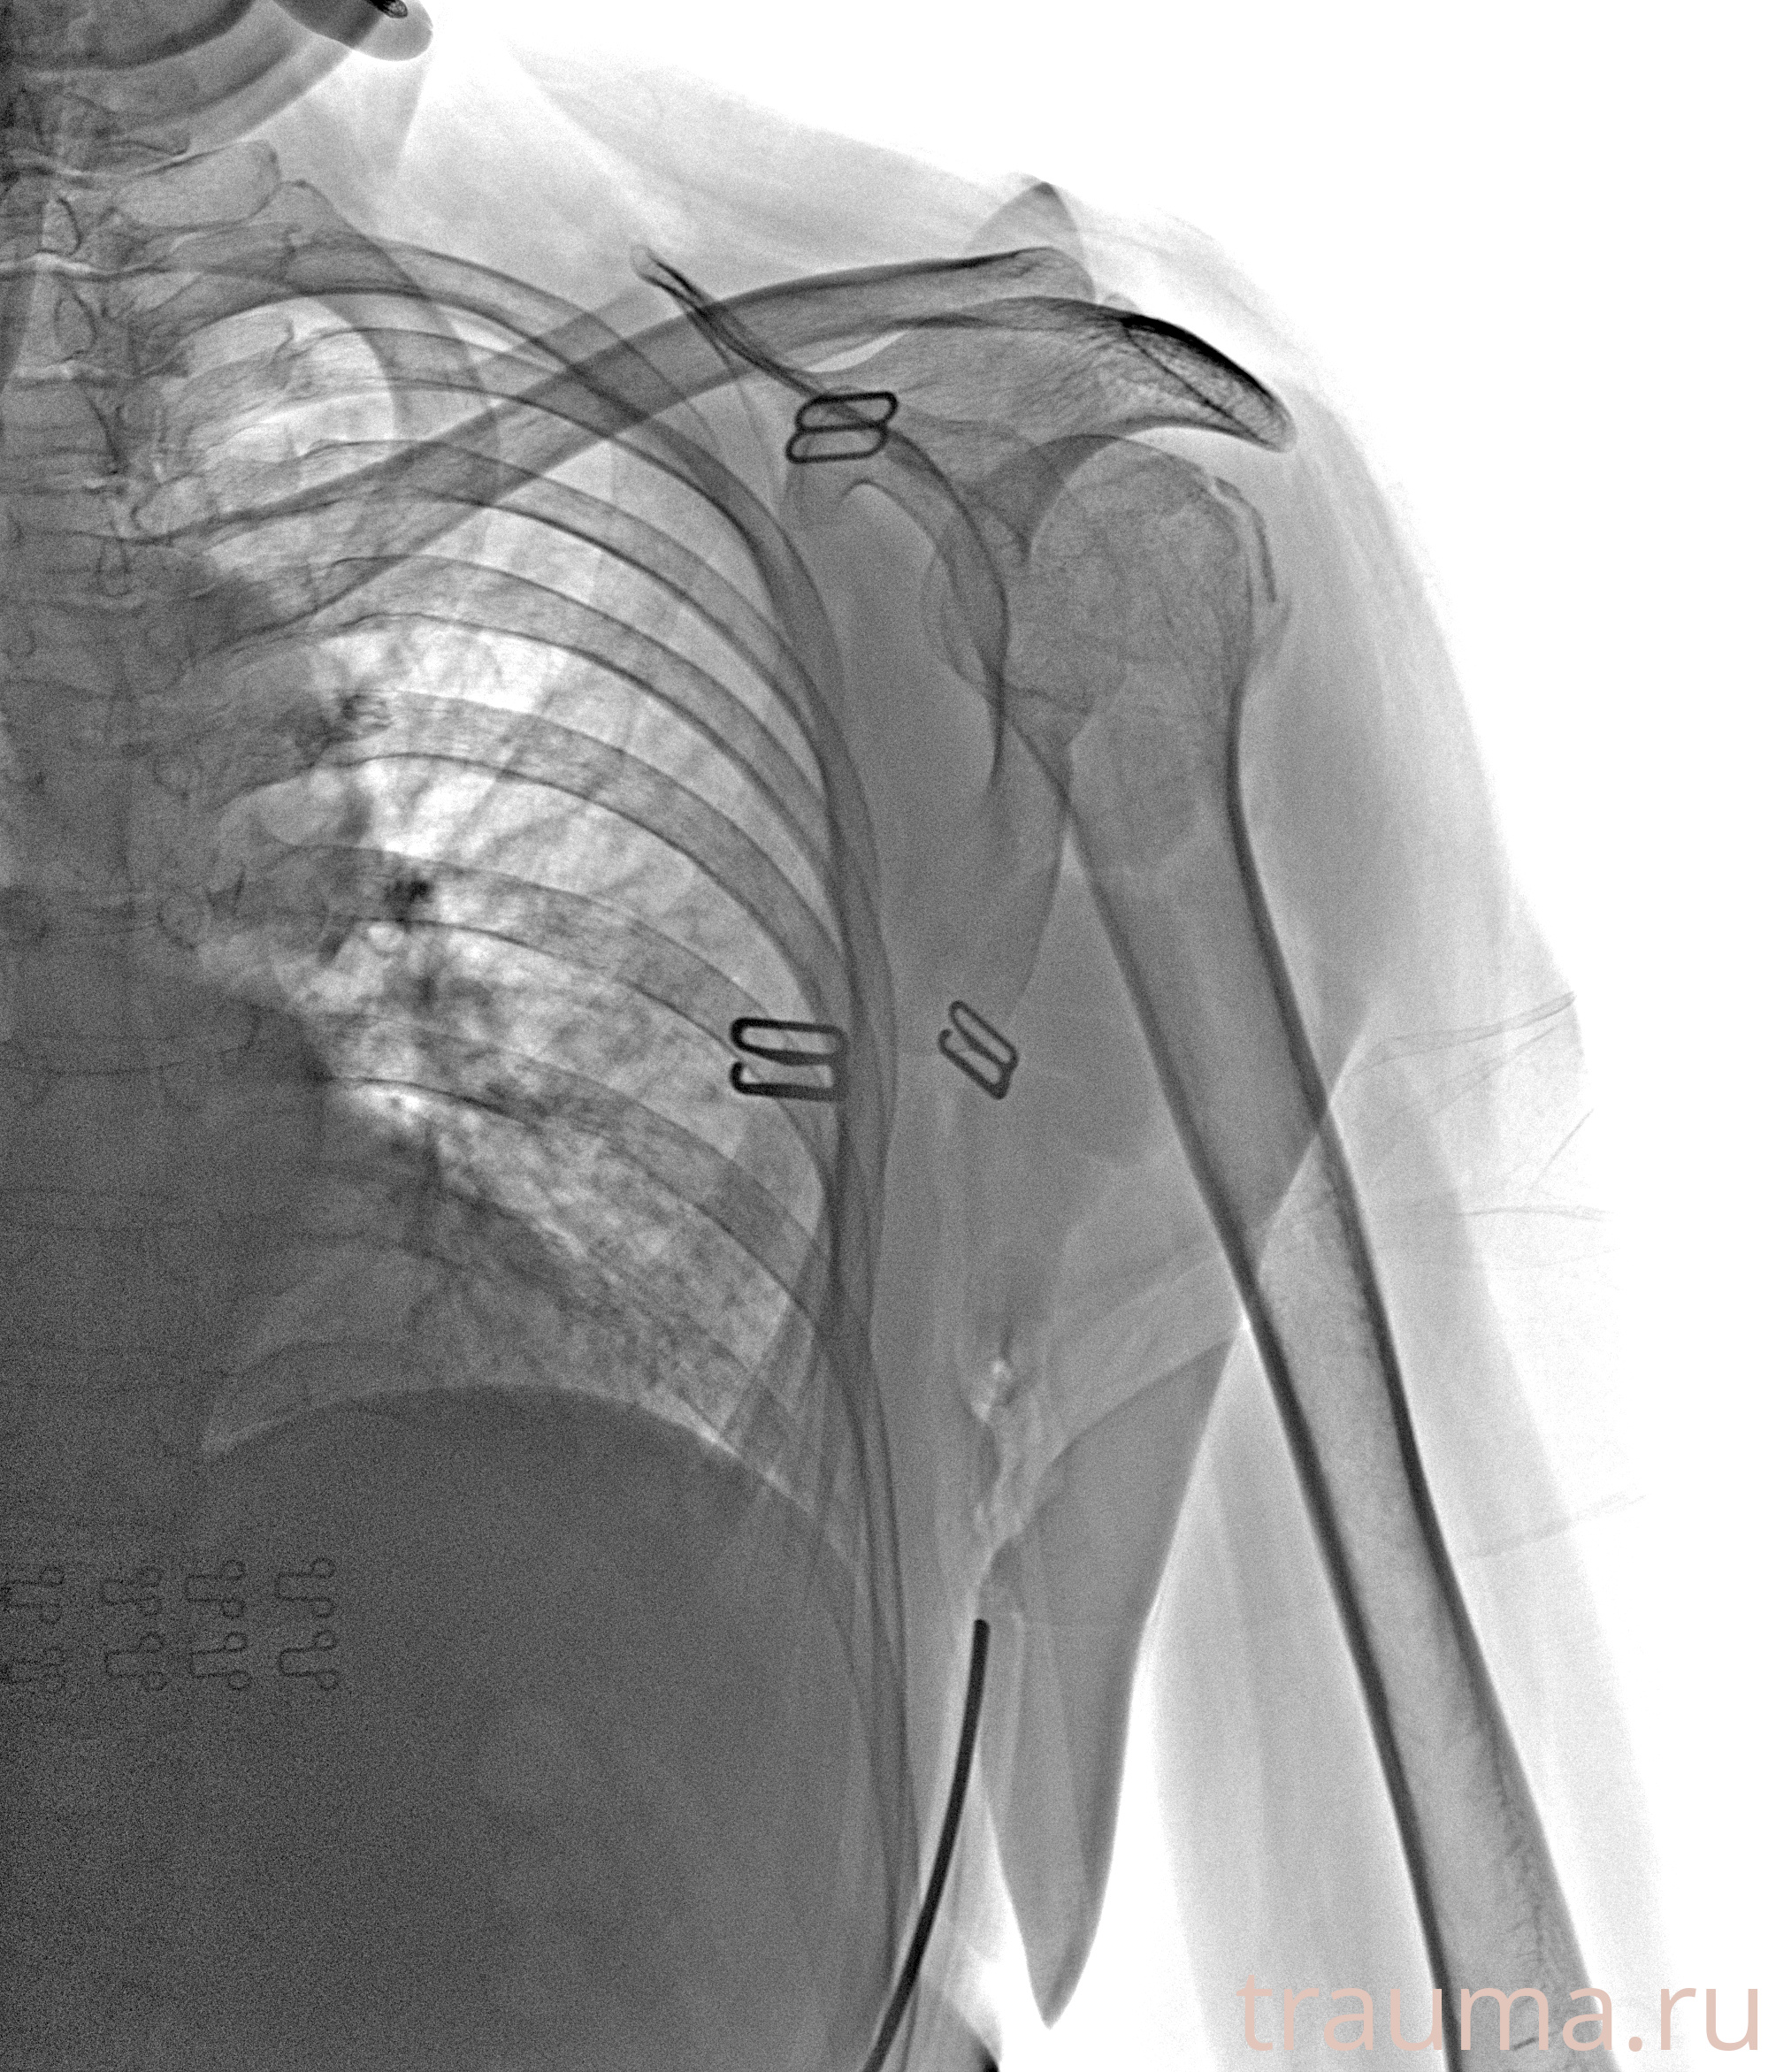

Рентгенограммы

Рентген на дому: по вашему адресу приезжает врач-рентгенолог, травматолог-ортопед с мобильным рентгеновским аппаратом, проводит диагностику травмы или заболевания, делает необходимые рентгенограммы, дает рекомендации по дальнейшему лечению. Получить качественные снимки в домашних условиях возможно благодаря уникальной методике, разработанной МосРентген Центром для института  Склифосовского